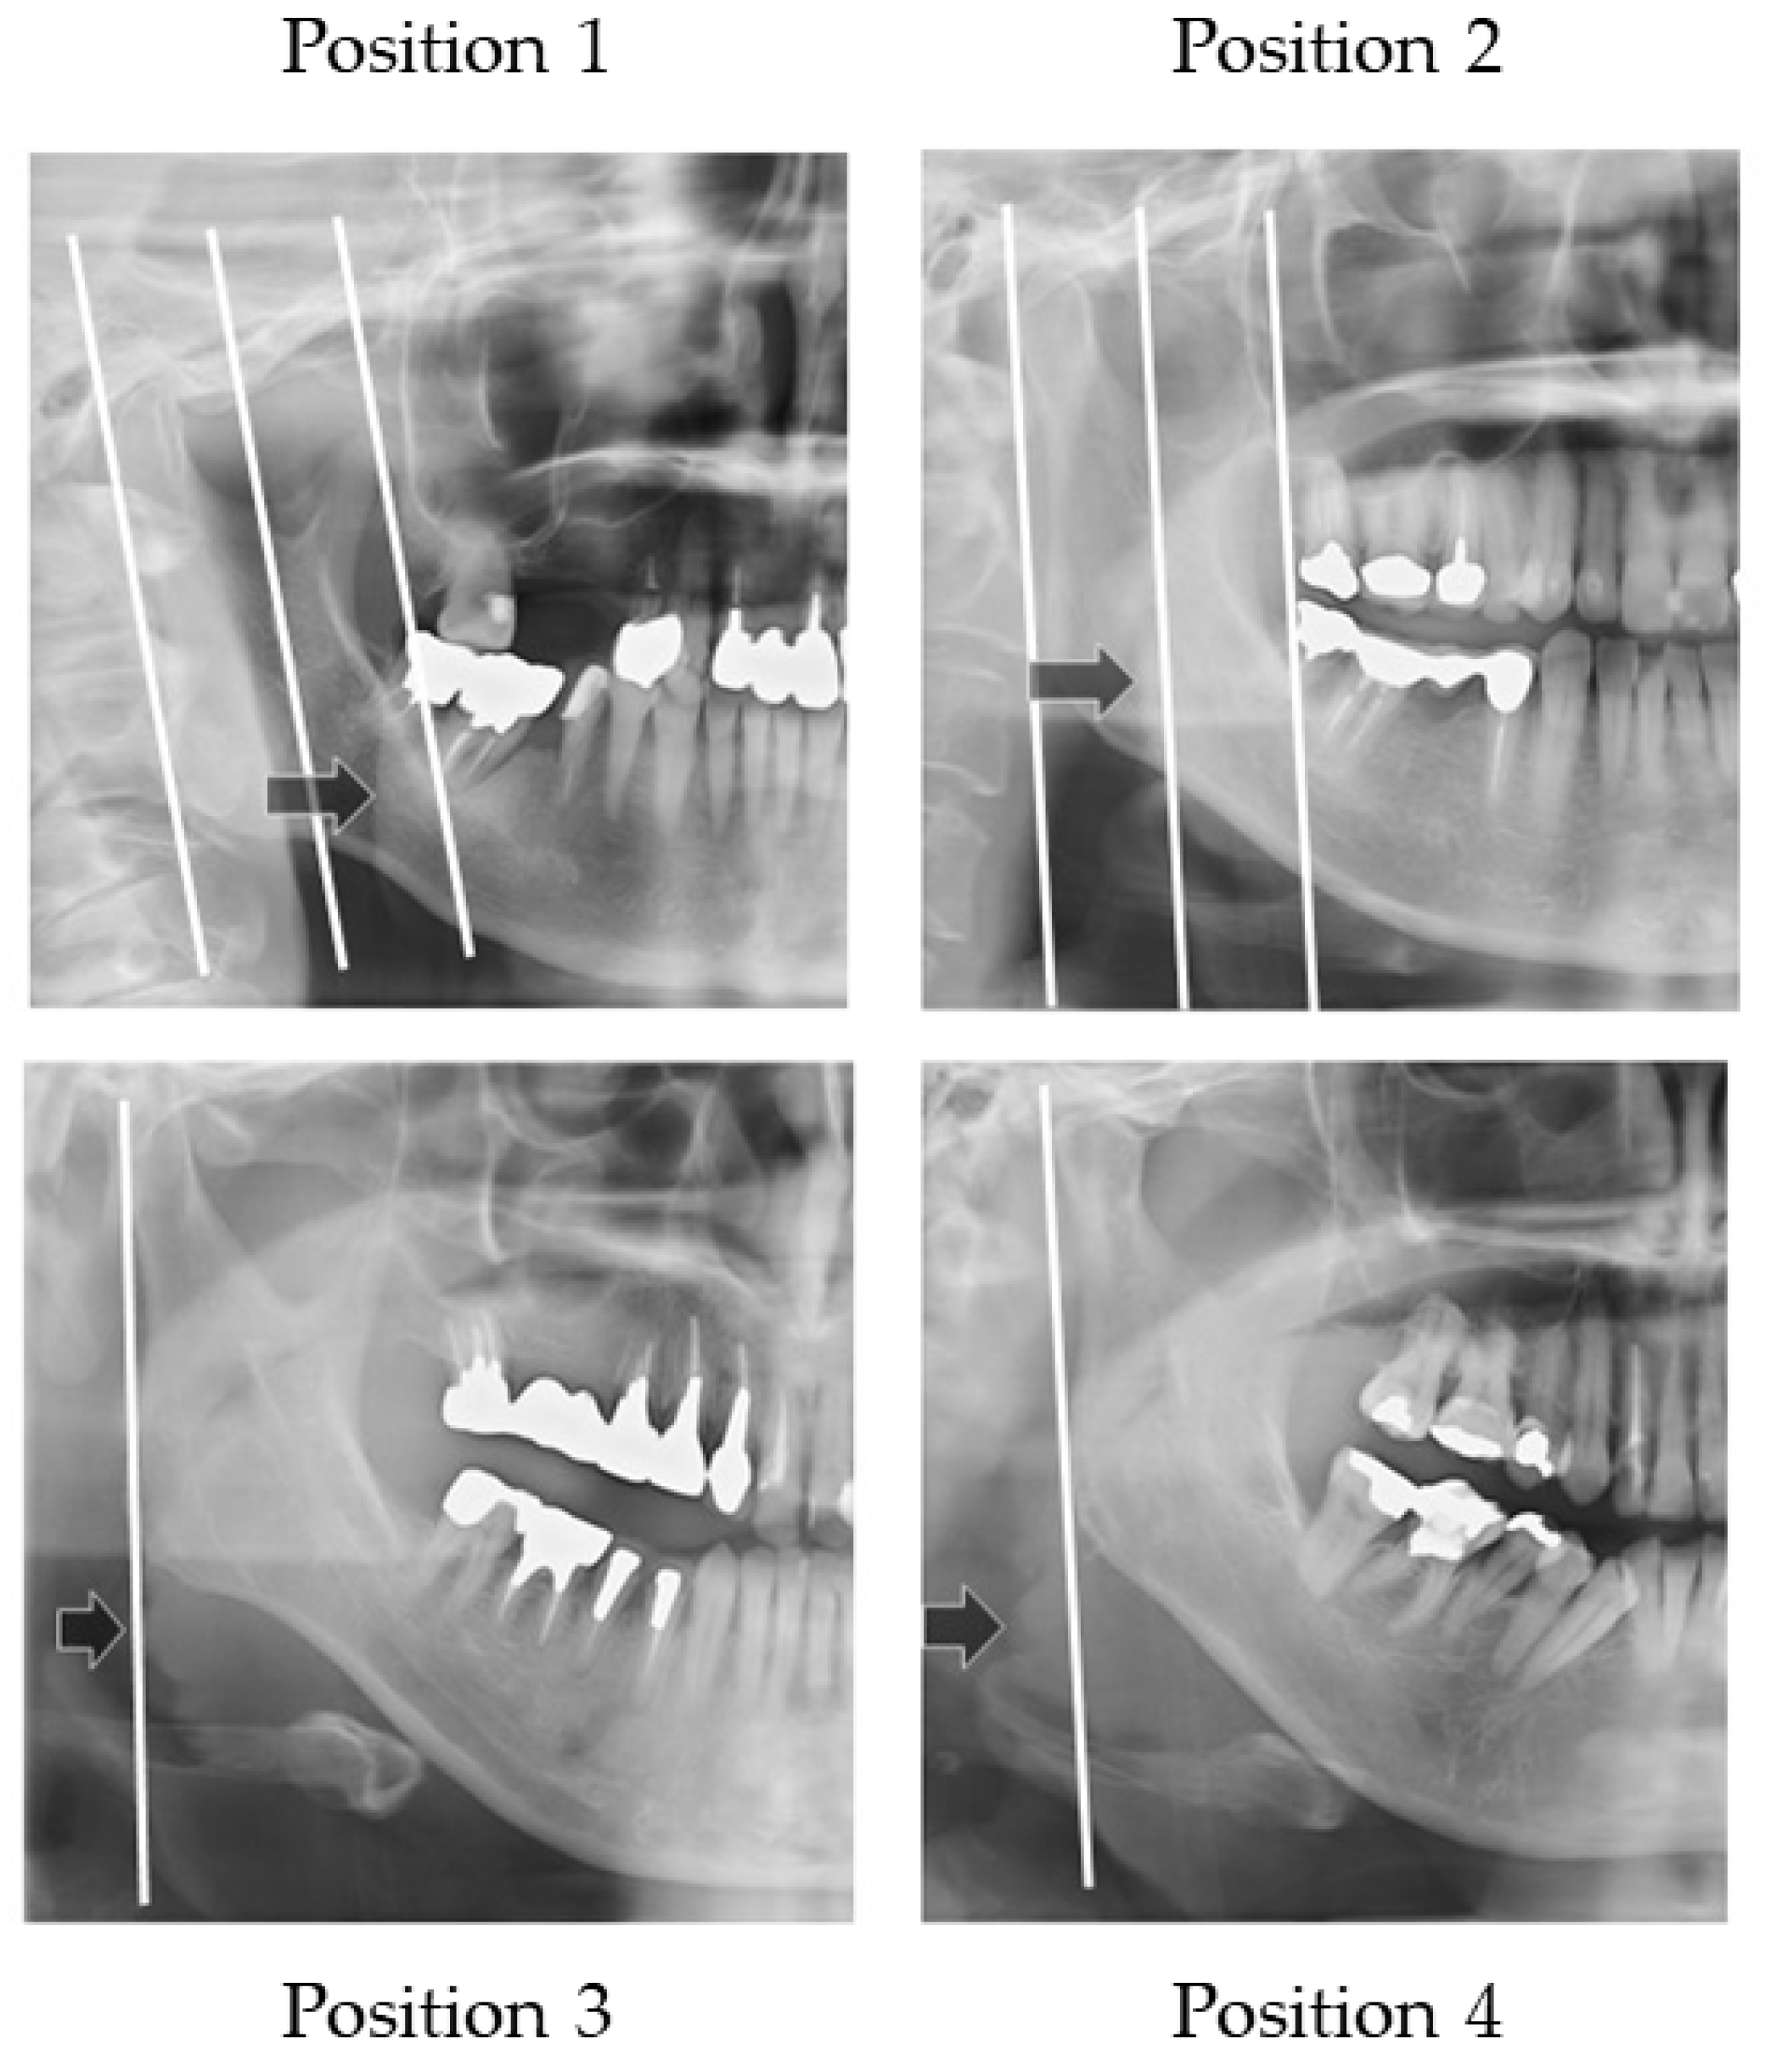

2.4.4. Width of Tongue

- The distal border of the mandible line is a simulated line, which is defined between the posterior point of the mandibular condyle and posterior point of the angle of the mandible.

- The mesial border of the mandible line is defined as the line that is the distal border line moved in parallel to the coronoid process.

- The midline of the border of the mandible line is defined as the midline of the distal border of the mandible line and the mesial border of the mandible line.

| Outer Border of Tongue | Dysphagia (+) | Dysphagia (−) |

|---|---|---|

| Position 1 | 4 | 3 |

| Position 2 | 18 | 8 |

| Position 3 | 13 | 12 |

| Position 4 | 12 | 7 |